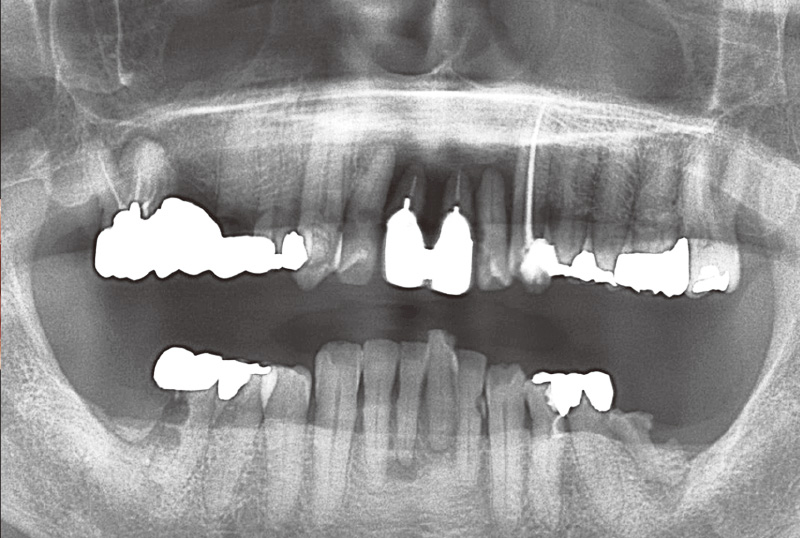

症例の患者さんは、奥様の介護があり毎日忙しくされていることもあってか、とにかくプラークコントロールが不良で、改善の兆しが見えませんでした。初診から6年が経過し、その間補綴治療を行ってきましたが、相変わらず磨き残しは目立っていました(図3)。そのため、染め出し後に「PrimescanConnect」でスキャンしたデータをお見せしたところ、「こんなにも磨き残しがあるとは思ってなかった」と、とても驚かれ、それ以降セルフケアの意識が向上し、磨き残しは大幅に減少しました(図4~6)。

図3 その後下顎に2本(₆ ₆)、上顎に1本(₆)のインプラントを埋入。写真は初診から6年後の染め出し写真。プラークコントロールが不良で、常に磨き残しが見られた。 -